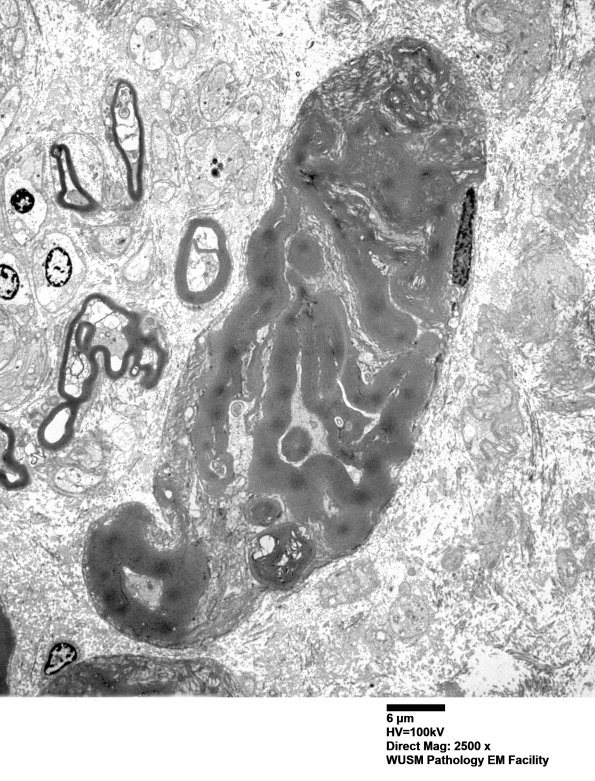

Additional examples of large axons with crush artifact. (electron micrographs)